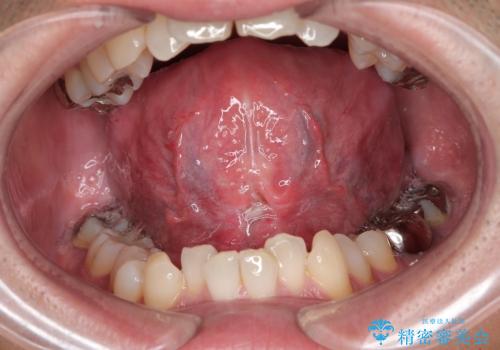

前歯の隙間とへこみが舌で触ると気になる|矯正治療は絶対にしたくない|抜歯即時インプラント+オールセラミッククラウンで審美修復

外科処置は一度だけ|抜歯即時インプラントで短期間で自然な見た目へ